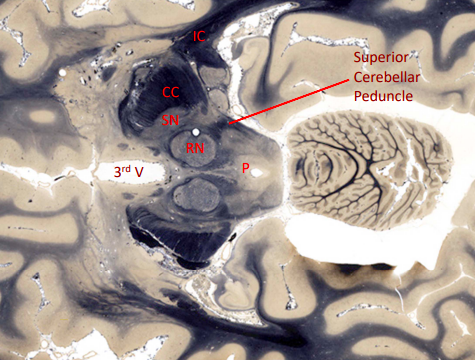

which cerebellar peundcle connects to the midbrain?

superior cerebellar peduncle - connects to the red nuclei of tegmnetum (deepest portion)